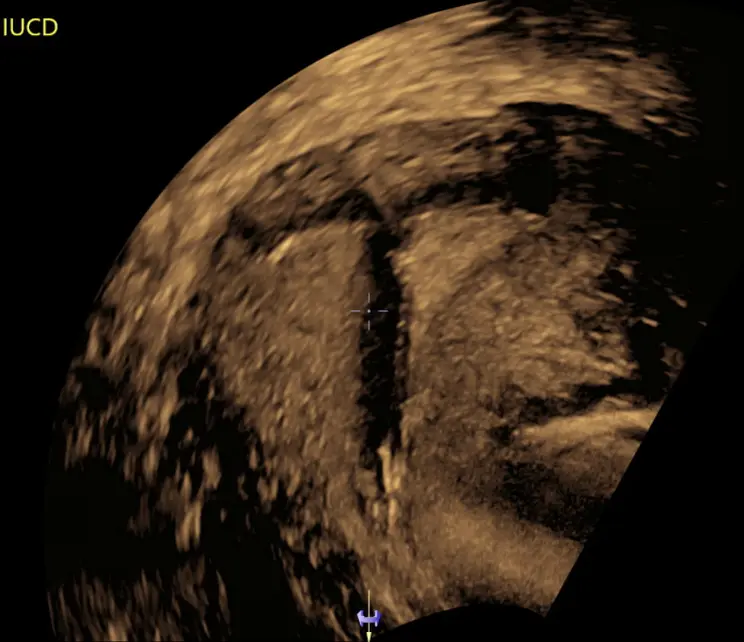

Placement, location, and removal of Intrauterine Device (e.g Mirena)

An Intrauterine Device (IUD) assessment, including 3D imaging, is a routine part of a gynaecological ultrasound examination.

When working correctly, an IUD should not not cause any unusual symptoms. IUD assessments are generally performed when a woman has symptoms that suggest a potential issue with her IUD (like pelvic pain or abnormal bleeding), or when a healthcare provider is unable to locate the strings of the IUD during a physical examination.

Position of the IUD: The assessment verifies that the IUD is in the correct position within the uterus.